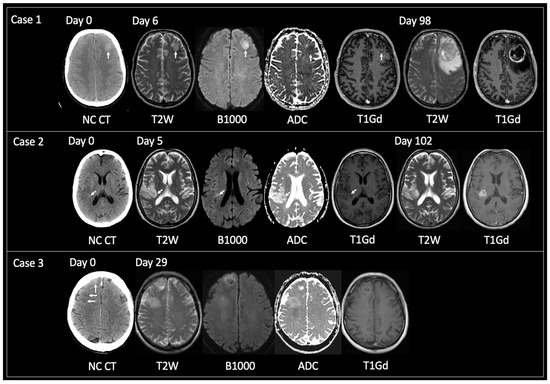

Mean time from CT hyperdensity to TRA GBM (n = 38) = 74 days (range 7–158); solitary lesions only (n = 32) = 69 days (7–158); >1 locus only (n = 6) = 95 days (46–147). Figure 3 displays examples of solitary lesions with TRA GBM at the time of tissue sampling with preceding imaging. Note cases 2 and 3 that show intratumoral foci of CT hyperdensity that progress at a faster rate than the rest of the tumor.

Figure 3.

Examples of solitary lesions with TRA GBM at tissue diagnosis that had preceding imaging. Case 1: 56-year-old male presented with seizures. Unenhanced CT on day 0 showed a hyperdense lesion in the left frontal lobe. This had corresponding T2 iso signal with reduced diffusivity and central nodular enhancement on MRI day 6. TRA GBM followed on MRI day 98. Case 2: 53-year-old female presented with several days of intermittent left-sided anesthesia. Initial unenhanced CT day 0 showed a focus of hyperdensity within the posterior aspect of the right insula (arrow) with adjacent cortical low density. MRI day 5 revealed an infiltrative glioma within the right inferior parietal lobule and right insular with the focus of prior CT hyperdensity corresponding to T2 iso signal, reduced diffusivity and containing a tiny dot of enhancement (arrows). MRI day 102 showed TRA GBM at the site of the prior CT hyperdense focus but relative stability of the rest of the non-enhancing tumor. Case 3: 63-year-old male presented with seizures. Unenhanced CT day 0 revealed two abnormal areas: a hyperdense focus anteriorly in the right superior frontal gyrus (vertical arrow) and subcortical hypodensity in the right middle frontal gyrus (horizontal arrows). These foci were linked by hypodensity (not shown) correlating with one diffuse tumor. MRI day 29 demonstrated interval growth of the previously hyperdense lesion, showing TRA GBM with enhancing periphery and central necrosis. Note how the peripheral tumoral tissue shows T2 iso solid signal with reduced diffusivity and enhancement. MRI day 29 also showed progression of the previously low-density lesion but not to TRA GBM. This lesion was shown to infiltrate into the deep white matter of the right centrum semiovale, contain areas of reduced diffusivity but no enhancement. TRA GBM—typical radiological appearance of glioblastoma, NC CT—non-contrast CT, T2W—T2-weighted, B1000—DWI, ADC—apparent diffusion coefficient map of DWI, T1Gd—T1-weighted post-gadolinium.